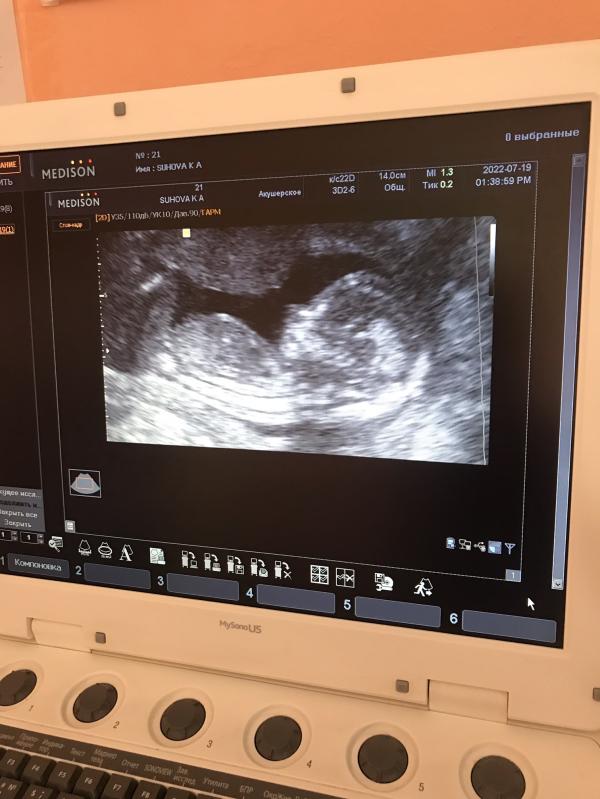

Сходила на первый «скрининг»😁

Оказывается не 12 недель , а все 15 как я и предполагала 🤷♀️

Скрининг не сделали , но уже скоро второй😍

По узи всё хорошо 🥰

Ого) какой уже большой ребёнок оказался)